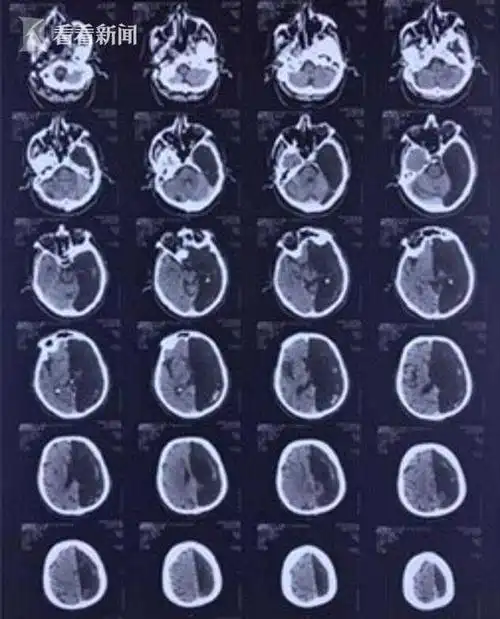

原创神奇60岁老人做头部ct左脑是空的仅靠半个大脑存活